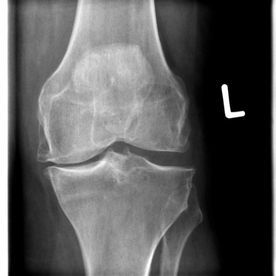

Varusgonarthose

(Knieverschleiß innenseitig)

Varusgonarthose (Kniegelenkverschleiß innenseitig)